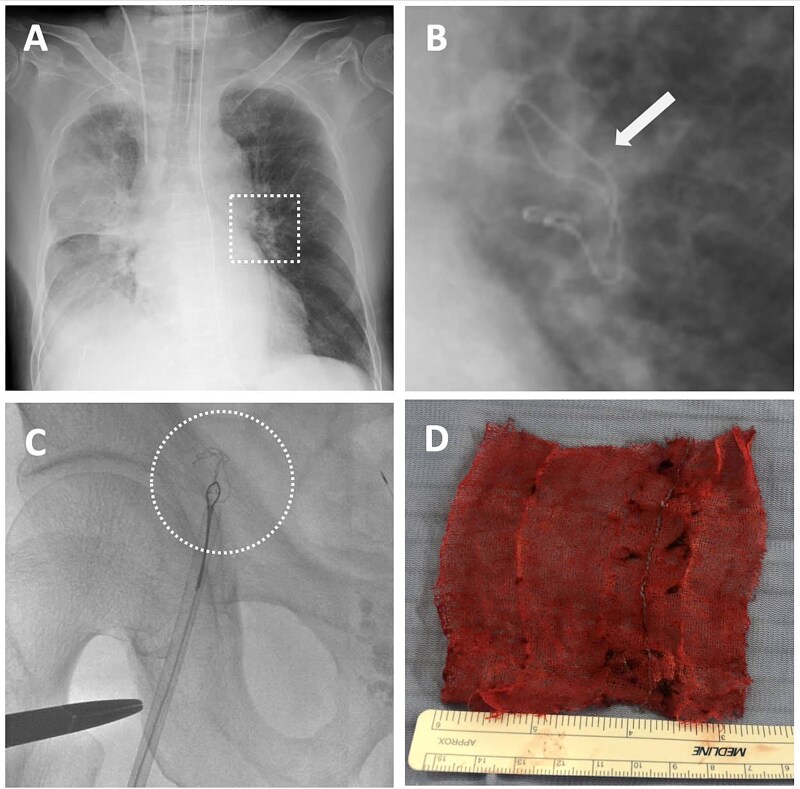

We report a case involving a hepatocellular carcinoma with massive bleeding from a large (retrohepatic inferior vena cava) RHIVC laceration during laparoscopic posterior sectionectomy, complicated by the exceedingly rare migration of surgical gauze into the left pulmonary artery (LPA). Hemostasis was achieved by manual compression and two anchoring Prolene sutures at both ends of the laceration, allowing effective RHIVC wall approximation. Given the low central venous pressure during hepatectomy, edge approximation significantly reduced bleeding and improved repair visibility. Postoperative imaging showed the gauze was lodged in the LPA, constituting an intravascular foreign body (IFB). The gauze was successfully retrieved via endovascular intervention without additional complications. Anchoring sutures with manual compression may be a helpful technique for managing a large RHIVC injury, and endovascular retrieval may provide a safe alternative to reoperation for a large IFB.